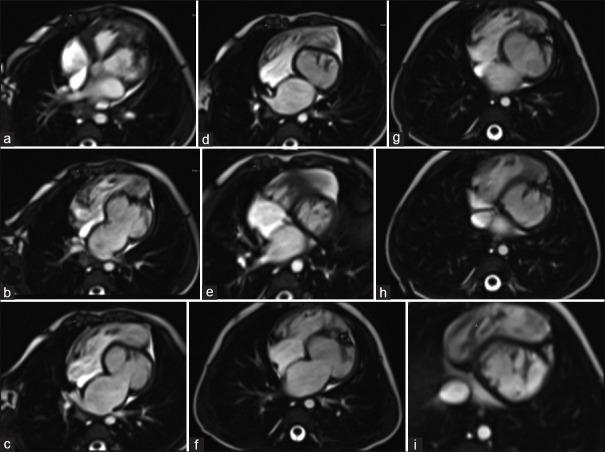

Isolated left ventricular hypoplasia is an entity with uncertain natural history and etiology. The presentation could vary from being asymptomatic to sudden death. This form of cardiomyopathy has been reported in infants as well as in adults. This case report aims to alert physicians to this diagnosis and the undeniable advantage of cardiac magnetic resonance.

孤立性左心室发育不全是一种自然病史和病因不明的病症。其表现可能从无症状到猝死不等。这种心肌病在婴儿和成人中均有报道。本病例报告旨在提醒医生注意这一诊断以及心脏磁共振成像不可否认的优势。